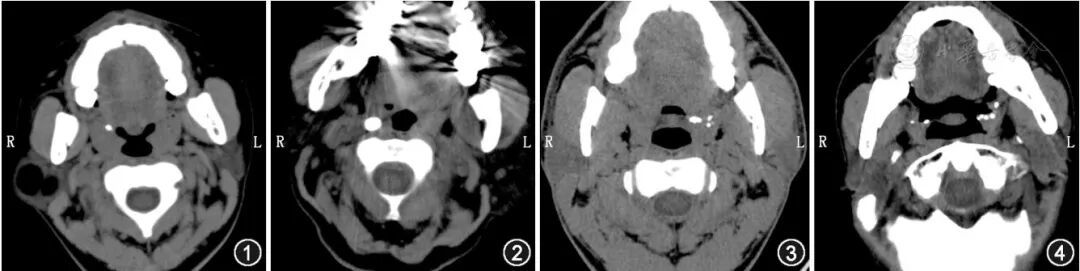

扁桃体结石常单侧发病,结石大小不一,小者如沙粒,大者如鸽卵。临床表现类似于慢性咽炎的症状,主要是反复咽痛、咽部异物感及伴有口臭。扁桃体结石的主要成分是磷酸盐,所以CT上呈致密影。

上图分别为CT显示的:右侧扁桃体单发小结石、右侧扁桃体单发较大结石、左侧扁桃体多发结石、双侧扁桃体多发结石

丨参考文献1